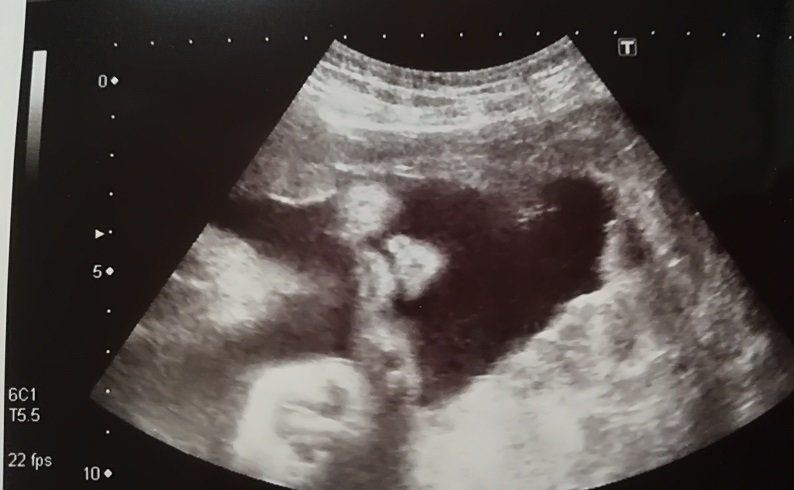

妊娠11週目のエコー写真

頭がはっきり確認できました。そろそろ、つわりがマシになるはずなのに、今度は喉が塞がる感覚で物が飲み込みにくくなるという症状が現れました。耳鼻科では、心身症を疑われて落ち込みました。点滴のおかげか、尿にケトン体が出るまでには至りませんでした。毎日、ネットで他の人のつわりが何週目で終わったのかを調べて励みにしましたが、実際うつ状態だったと思います。